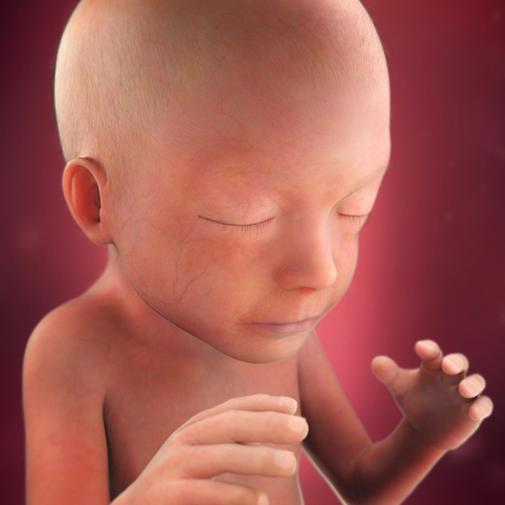

Hlavička se pomalu přizpůsobuje velikosti těla, ale i přesto stále zabírá jednu třetinu velikosti celého tělíčka. Jeho pohyby jsou dokonalejší, zlepšuje se hmat, dítě si cucá paleček, hladí si obličej nebo si hraje s pupeční šňůrou. Polyká velké množství plodové vody. Ke konci těhotenství to bude až půl litru plodové vody během 24 hodin. Rostou mu nehty, vlásky i chloupky. Odpadní látky jsou filtrovány částečně ledvinami plodu, částečně ledvinami matky. Na jazyku jsou již chuťové pohárky.

Pro určení délky plodu se nyní používá součet délky hlavičky, trupu a nohou. Ve 21. týdnu těhotenství měří plod zhruba 26,5 cm. Váha plodu je nyní zhruba 360 g.